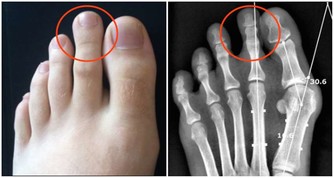

常常食用可以刺激身體排毒,應對由於身體毒素累積所造成的疾病,

如風濕、關節炎等。另外,芹菜還可以調節體內水分的平衡,改善睡眠。